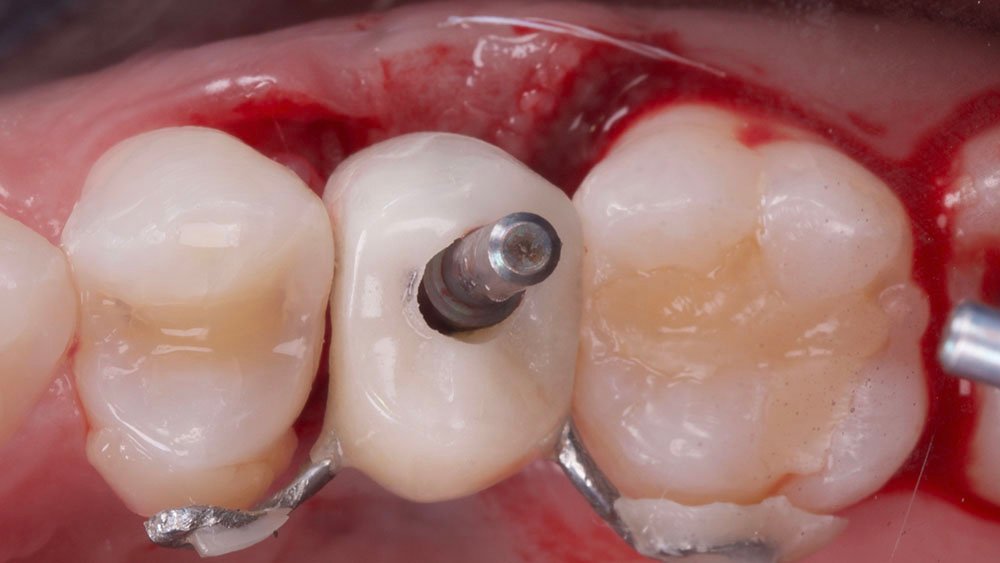

Confeccionou-se um dente provisório aparafusado com coifa de titânio 4,5 x 4 mm – Linha Ideale (Implacil De Bortoli, São Paulo-Brasil), sobre o Pilar Ideale 4,5 x 4 x 2,5 (Implacil De Bortoli, São Paulo-Brasil), apoiado no Implante Maestro 4 x 11 (Implacil De Bortoli, São Paulo-Brasil), obtendo um torque aproximado de 40N. E por fim, realizou-se a proservação e acompanhamento radiográfico.